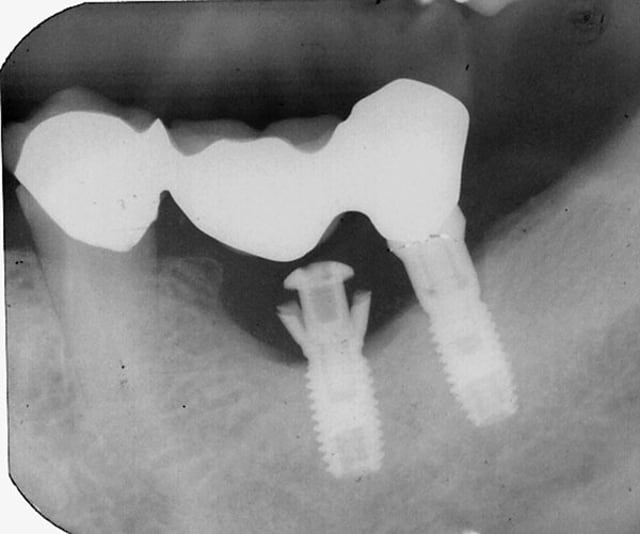

Faut pas croire que la créativité se limite à la pédodontie.

En implanto aussi, ya des pointures . Voici mon coup de coeur de la semaine :